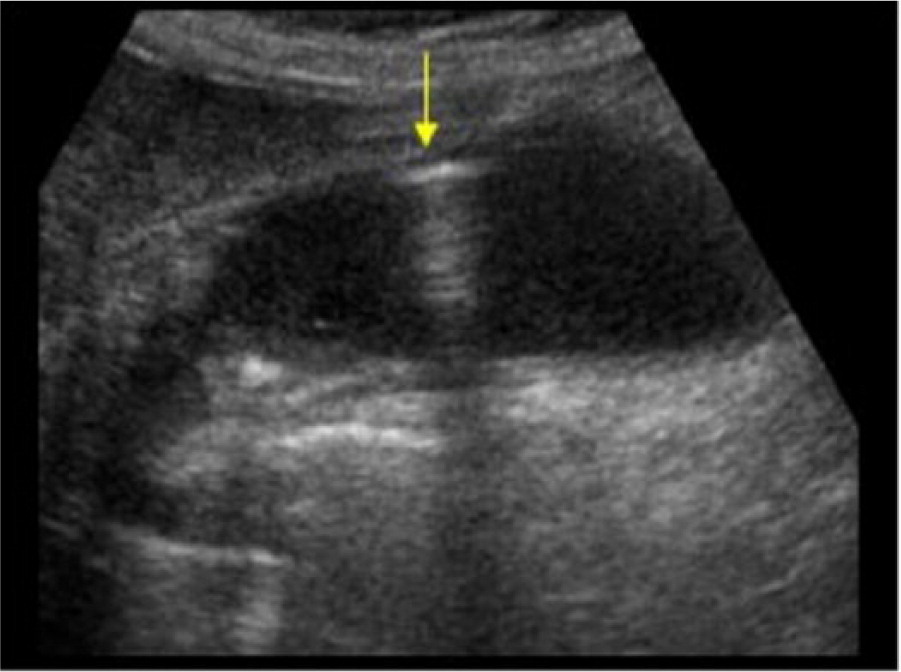

biliary atresia may show evidence of "triangular cord sign" which is an ____

avascular, echogenic, triangular or tubular structure anterior to the PV

what does the "triangular cord sign" represent?

replacement of the extrahepatic duct with fibrous tissue in the porta hepatis